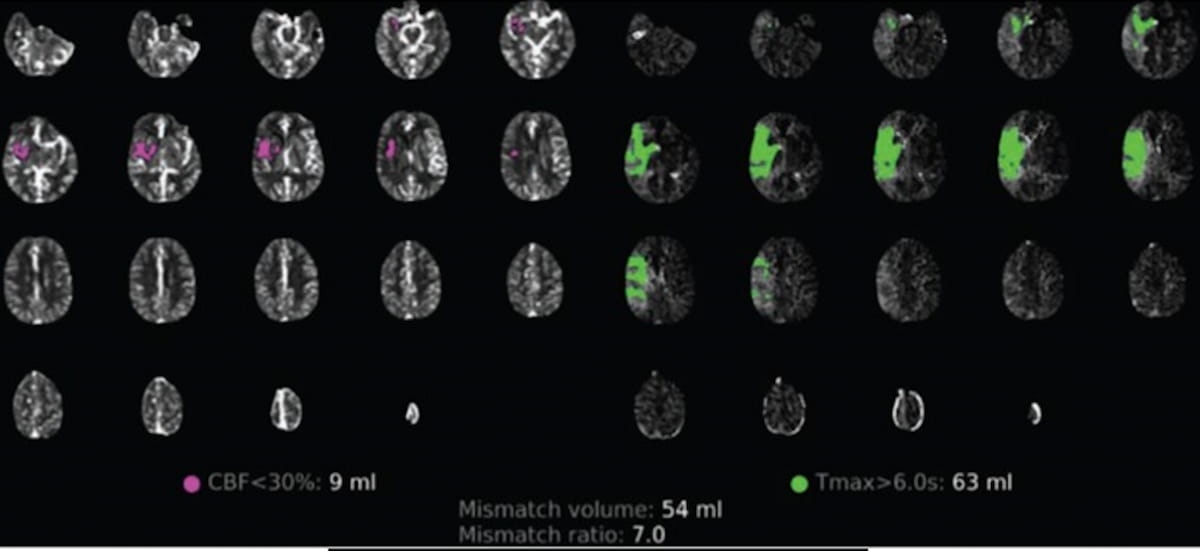

В ретроспективном исследовании, недавно опубликованном в Американском журнале рентгенологии , исследователи сравнили данные перфузионной компьютерной томографии (CTP) у 10 пациентов с положительным результатом на COVID-19 (средний возраст 67 лет), у которых был AIS, и у 144 контрольных пациентов с AIS без COVID-19. (средний возраст 71 год). Все пациенты подверглись эндоваскулярной реперфузии по поводу АИС, и авторы исследования рассмотрели визуализацию CTP до эндоваскулярной реперфузии, а также последующую визуализацию, включая магнитно-резонансную томографию (МРТ), когда она была получена, согласно исследованию.

Исследователи отметили, что первоначальная визуализация CTP до реперфузии показала очаг инфаркта 1,5 мл и общий объем гипоперфузии 85 мл у пациентов без COVID-19 по сравнению с исходным очагом инфаркта 30,5 мл и общим объемом гипоперфузии 117 мл у пациентов с COVID-19.

Постреперфузионная визуализация показала средний конечный объем инфаркта (FIV) 77,8 см3 у пациентов с COVID-19 по сравнению с 18,2 см3 в контрольной группе без COVID-19. Авторы исследования заявили, что после контроля уровня глюкозы и расширенного лечения церебральной ишемии (eTICI) скорректированные модели логистической параметрической регрессии показали, что COVID-19 был связан с отношением шансов 5,1 для абсолютного роста инфаркта на 15 см3 или более.

Изображения предоставлены Американским журналом рентгенологии .